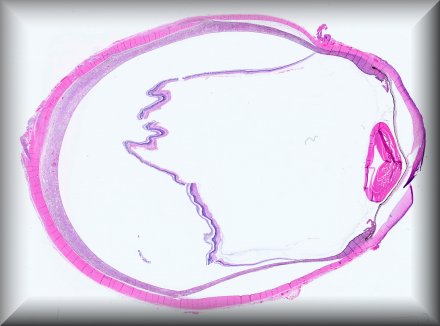

Jolique van Ipenburg (Nijmegen): 50-year-old male, retinoblastoma survivor, with conjunctival squamous lesion. Protocol |